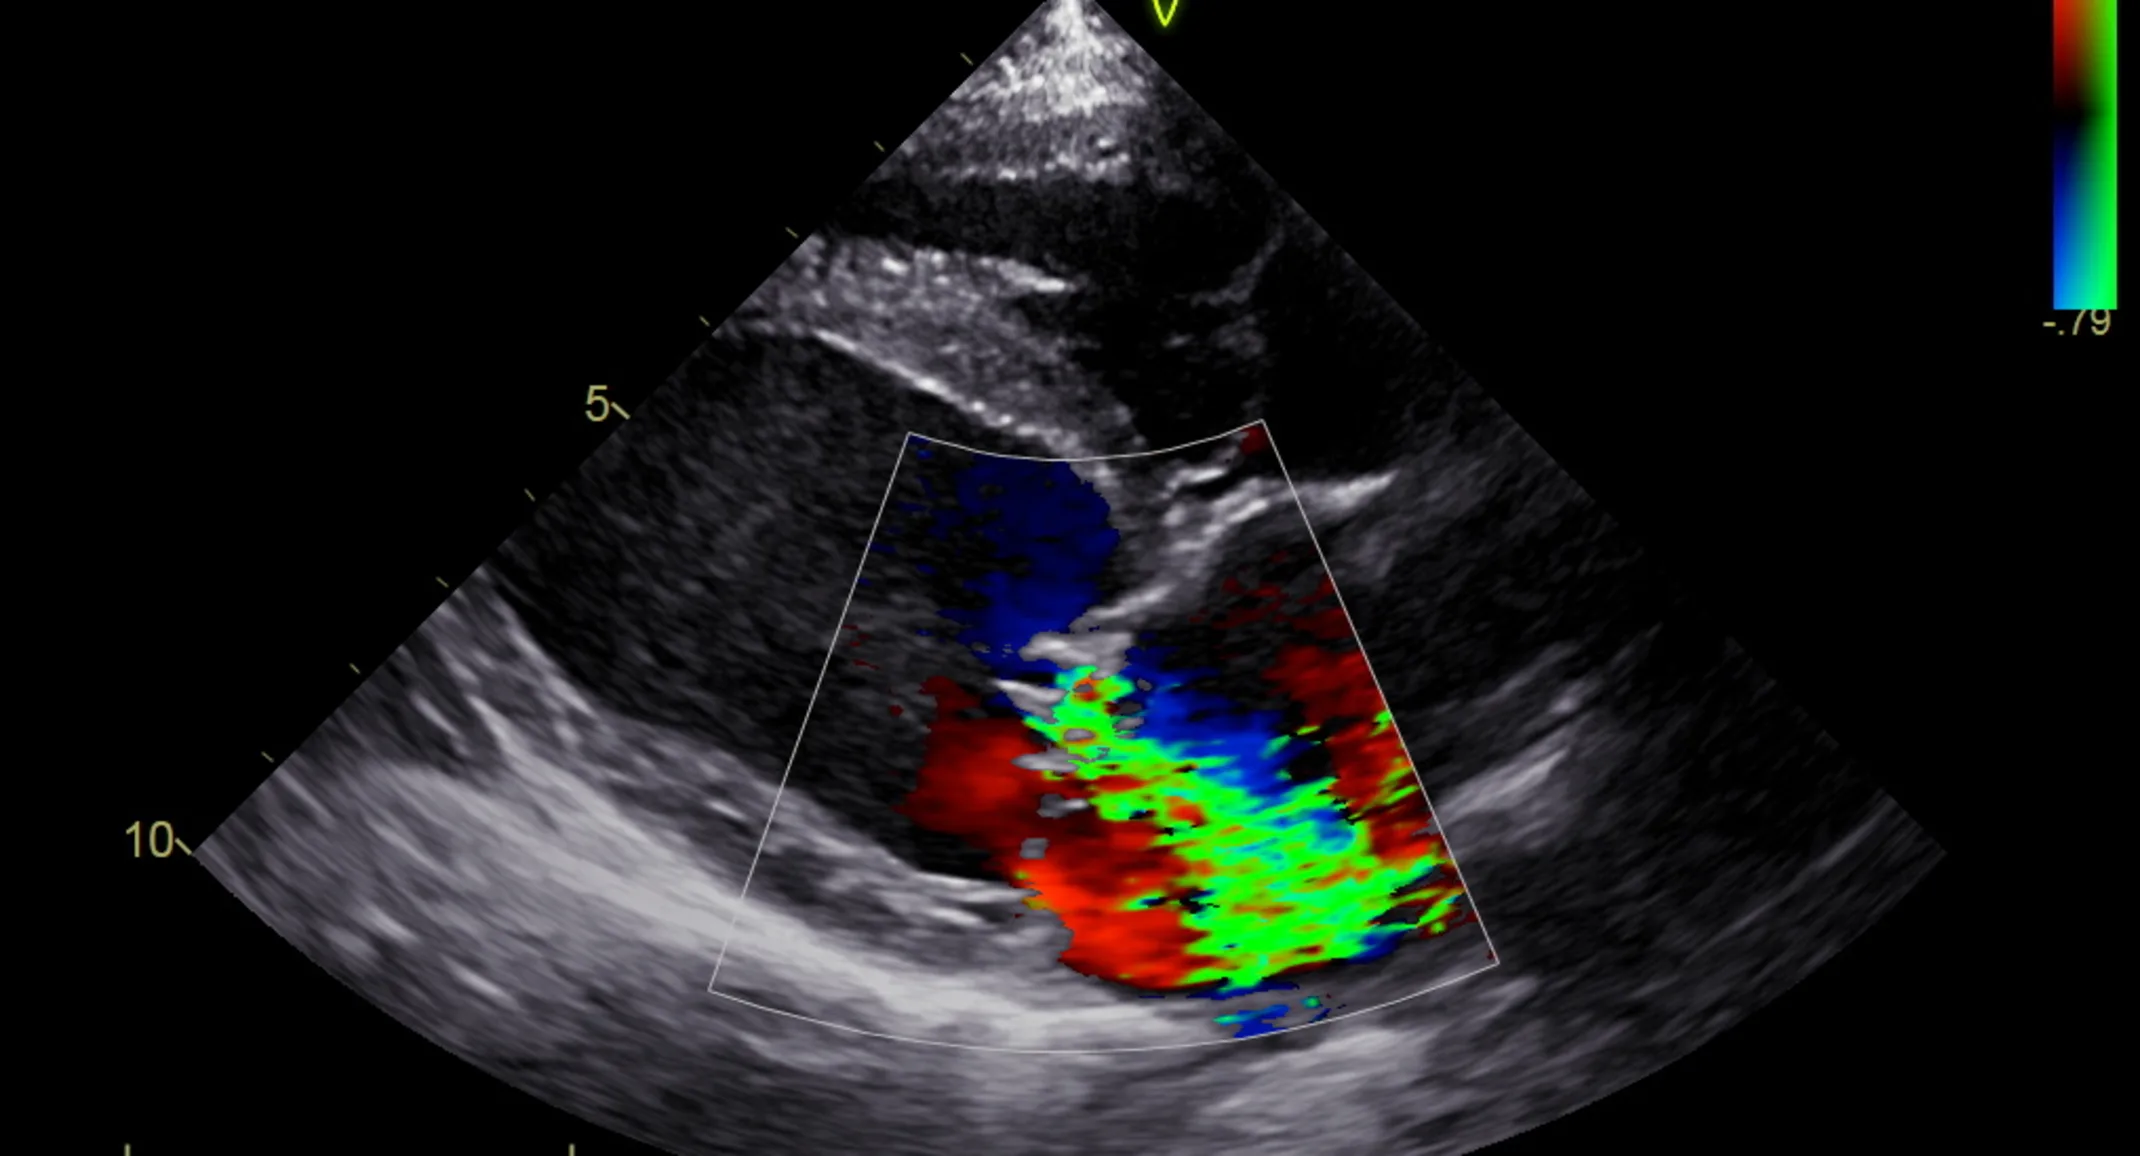

An echocardiogram (ultrasound of the heart) uses ultrasound waves to create real time images that allow the cardiologist to evaluate the heart size, valve function and heart strength. Most people are familiar with ultrasound technology that is used for a pregnancy sonogram. A veterinary cardiologist will use the same type of hand-held probe/scanner to image your pet’s heart. It is considered the most sensitive test for diagnosing heart disease in dogs and cats.